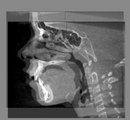

For assessment of overall facial changes, cranial base segmented models are only used to mask anatomic structures that change with growth and treatment. The registration procedures actually compare voxel by voxel of gray-level CBCT images, containing only the cranial base, to calculate rotation and translation parameters between the 2 images. Cranial base registration yields information of facial displacements relative to the cranial base. For subjects in whom cranial base growth is complete, registration is done using the gray level CBCT datasets of the whole cranial base ( Nongrowing registration module). The larger the number of voxels used for the registration, the more robust the registration is. For this reason, for adult patients the whole cranial base “mask CBCT” is used for registration. For growing patients ( Growing registration module), the registration includes two steps in the same module: in the first, an initial head alignment is done using the whole cranial base, and then a finer registration is performed at the stable structure on the anterior cranial base. For assessment of localized facial changes, such as mandibular or maxillary growth or bone remodeling of the mandibular condyle or tooth movement, specific anatomic regions can be used to create localized masks and aid regional superimpositions. The challenge in regional superimpositions is to determine which structures offer stable reference for registration.

• Mask creation: segmentation files are used to : 1: generate CBCT files that can be used to mask anatomic regions that changed with growth and treatment ; or 2: generate a CBCT file that contains only the anatomic region of interest for regional superimpositions.